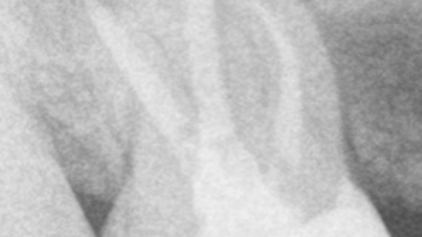

Los casos de retratamiento a menudo se complican y es por eso por lo que el retratamiento requiere…